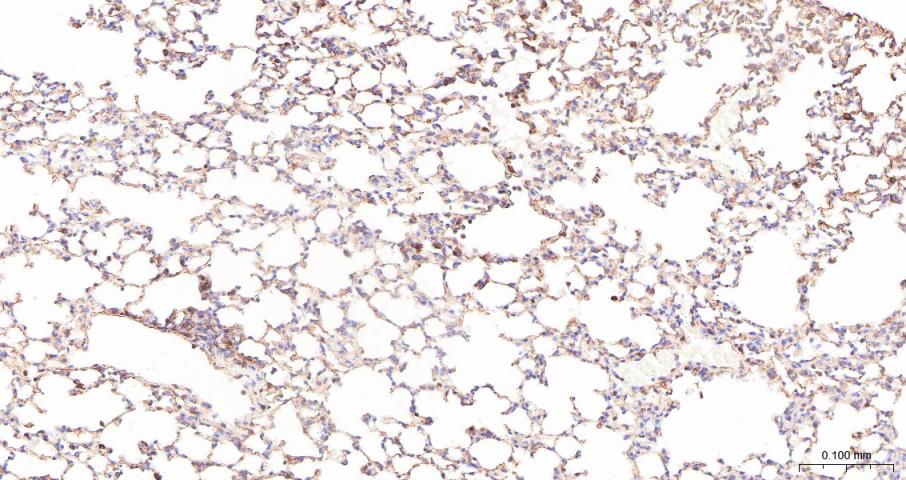

Paraformaldehyde-fixed, paraffin embedded Mouse Lung; Antigen retrieval by boiling in sodium citrate buffer (pH6.0) for 15 min; Antibody incubation with ADAM17 Polyclonal Antibody, Unconjugated (bs-4236R) at 1:200 overnight at 4°C, followed by conjugation to the bs-0295G-HRP and DAB (C-0010) staining.

Paraformaldehyde-fixed, paraffin embedded Rat Lung; Antigen retrieval by boiling in sodium citrate buffer (pH6.0) for 15 min; Antibody incubation with ADAM17 Polyclonal Antibody, Unconjugated (bs-4236R) at 1:200 overnight at 4°C, followed by conjugation to the bs-0295G-HRP and DAB (C-0010) staining.